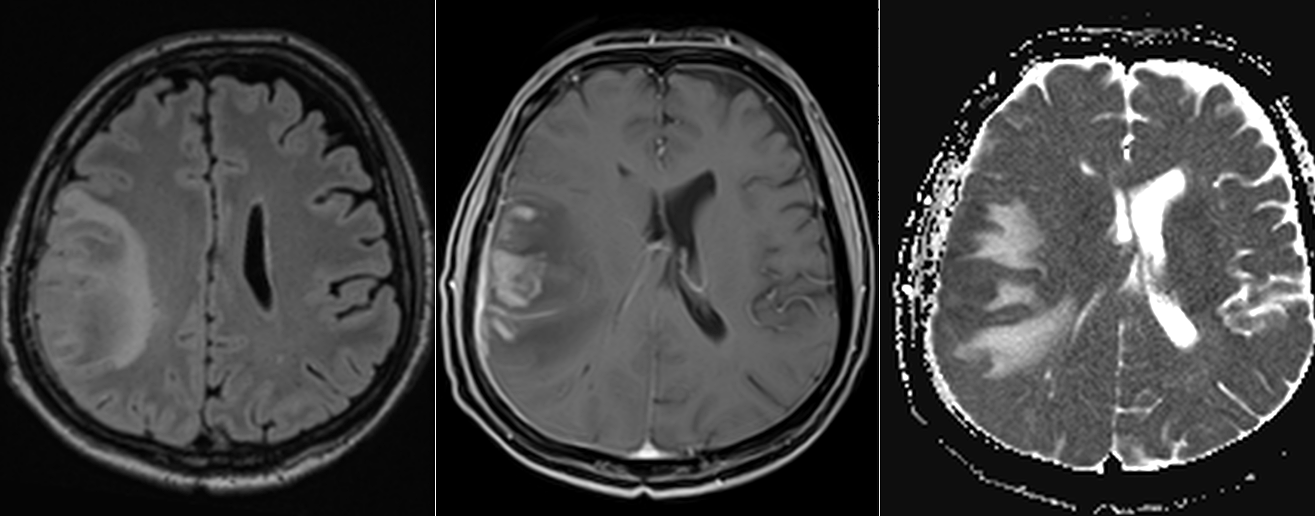

IRM cerebral cu substanță de contrast – metoda de elecție. Limfoamele sunt leziuni cu hipersemnal T2-FLAIR și hiposemnal T1, imprecis delimitate, cu contrast intens, adesea periventriculare si cu aspect caracteristic de difuzie (ADC). Poate mima glioblastomul sau metastazele cerebrale.